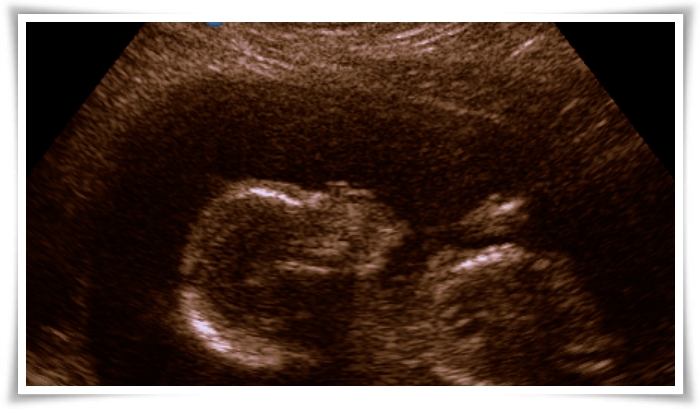

Se estamos felizes? Demaaais!!! Mal posso esperar pra ter essa bonequinha nos meus braços. E não é coisa de mãe coruja não, viu? Olhem o perfil da nossa pequena! Não é uma boneca? 😀

Ontem passamos noite na internet, varrendo listas de nomes e mais nomes de menina até que enfim encontramos o nome que tem a carinha da nossa princesa. Mas isso, só no próximo post… lá lá lá…